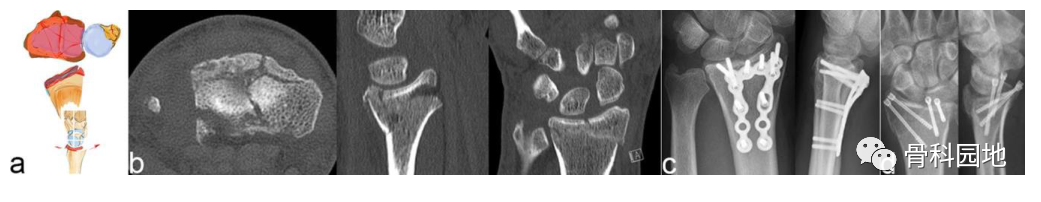

1、桡骨关键骨块

注:径向作用力沿头状骨、舟状骨和月骨指向茎突,茎突沿韧带止点断裂并沿桡侧掌侧或背侧方向脱位(见图a)。茎突和月骨形成一个由韧带连接的单元。在外伤的情况下,头状骨突出在月骨和舟骨之间,导致舟月韧带断裂。由于韧带附着,腕骨倾向于径向半脱位(见图 b)。

一、桡骨关键骨折

此类型骨折,最好用桡骨解剖板治疗(见图)。这些钢板具有较长的桡骨和较短的尺骨边界,这些桡骨板可以安装在很远的远端,从而抓住远端碎片。这种钢板的主要缺点是可能会损伤屈肌腱,具体取决于钢板的位置。克氏针引导的空心双头螺钉是治疗单个茎突骨折上位好方法,尤其是在关节镜辅助下进行手术。